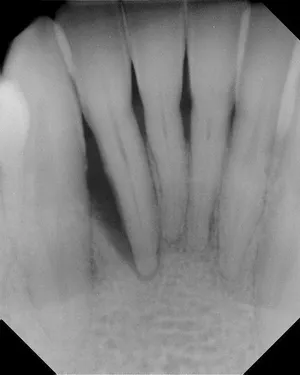

Before and After X-rays